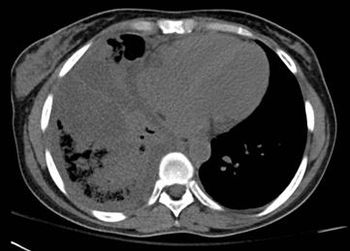

A young woman experienced acute onset of high fever, productive cough, and right-sided pleuritic pain. She was not in sickle cell crisis. Do the images here shed light on cause of symptoms?

Results of a physical examination and CT scan of the chest offer clues to this patient's diagnosis.